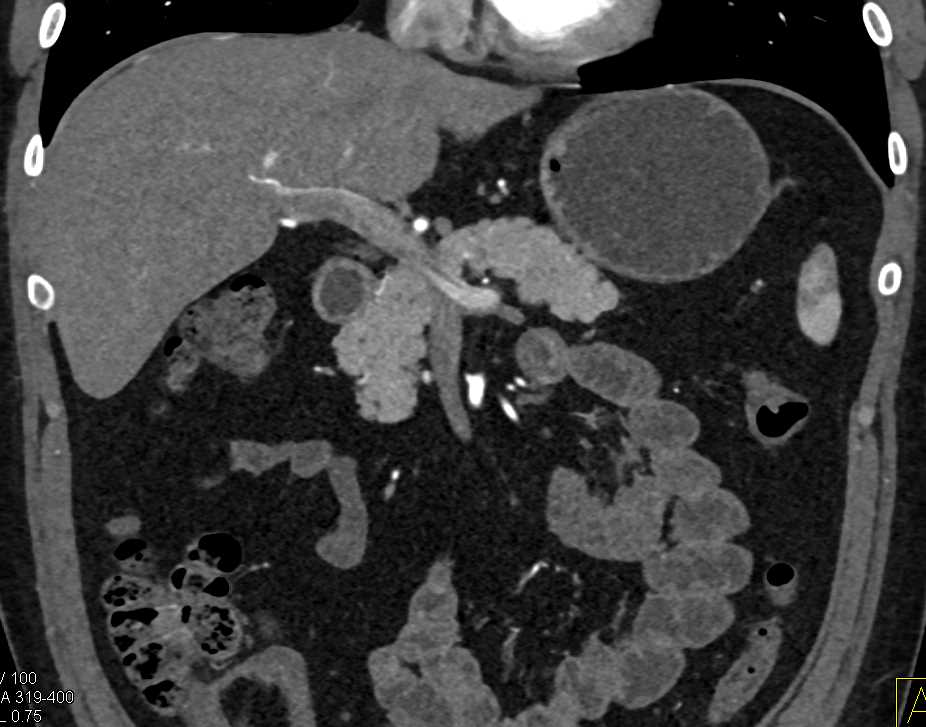

Neuroendocrine Tumor Body of Pancreas